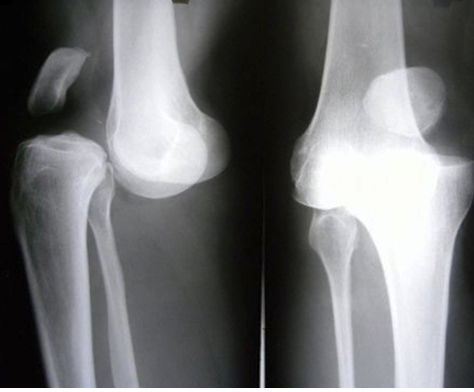

What is shown in this X-ray?

A

Patellar dislocation and knee dislocation